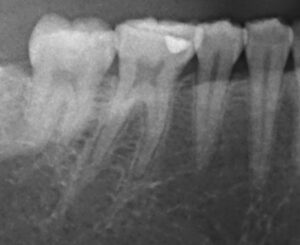

40歳男性の二次虫歯を顕微鏡根管治療